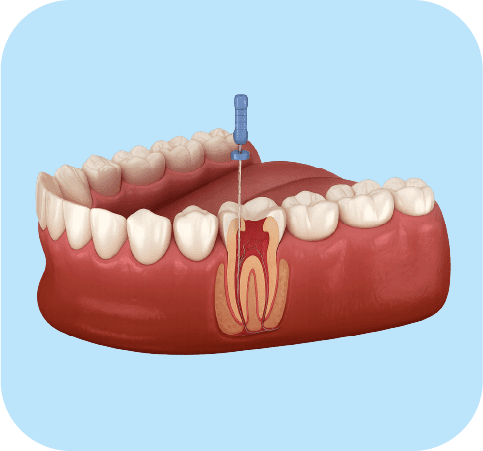

Root Canals (Endodontics)

From

Clinical evaluation and diagnosis

Complete root canal treatment per tooth

Use of rotary technology and electronic apex locator

Recommended for teeth with infection, pain, or advanced decay. Preserves the natural tooth and eliminates the source of infection.